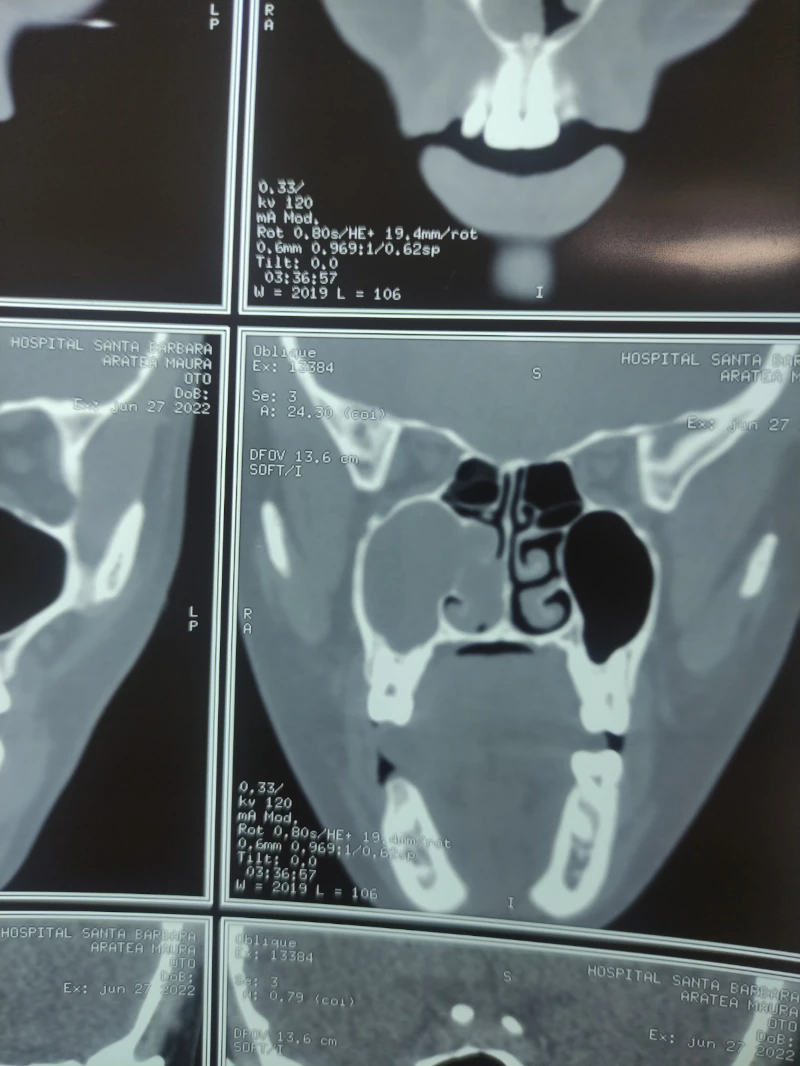

04. Sinusitis (infección de los senos paranasales)

03. Polipo nasal

08. Deformidad del tabique

02. Obstrucción nasal